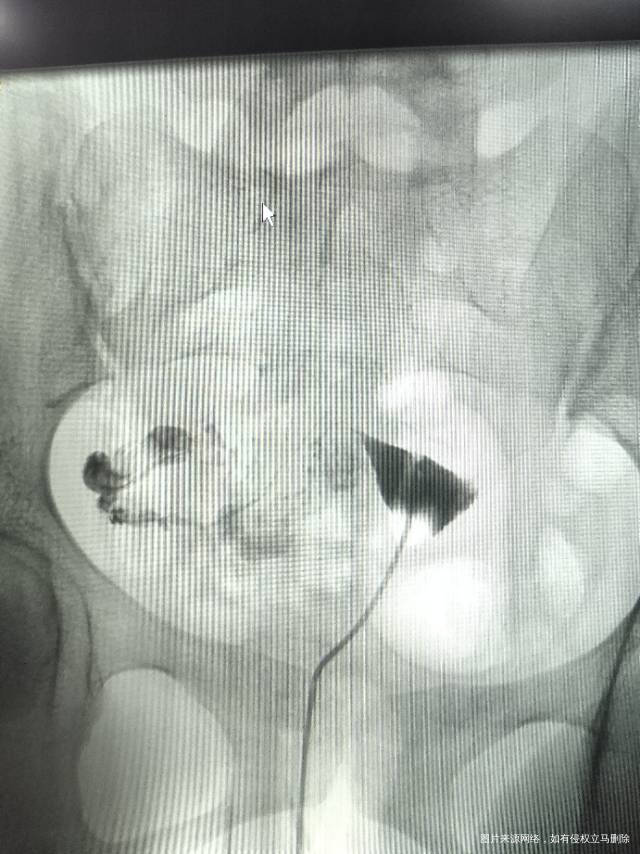

双侧输卵管堵塞,手术不能疏通,只能做试管,试管移植成功率在60-70%,建议尽快去生殖中心就诊,行移植前准备。